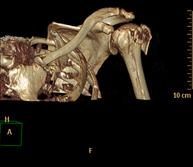

Prova diagnòstica no invasiva que consisteix en l'estudi vascular del sector aorto-ilíac i dels vasos arterials d'ambdues extremitats inferiors i l'obtenció d'imatges d'alta definició anatòmica mitjançant l'ús d'un equip de TC Multidetector d'última generació i de contrast iodat. La qualitat de les imatges permet realitzar reconstruccions en 2D i 3D gràcies a estacions de treball especialitzades en l'estudi arterial.

Prova diagnòstica no invasiva que consisteix en l'estudi de vascular del sector aorto-ílíac i dels vasos arterials d'ambdues extremitats inferiors amb l'obtenció d'imatges d'alta definició anatòmica mitjançant l'ús d'un equip de TC (Tomografia Computaritzada) i contrast iodat. La qualitat de les imatges permet realitzar reconstruccions en 2D i 3D gràcies a estacions de treball especialitzades en l'estudi arterial.